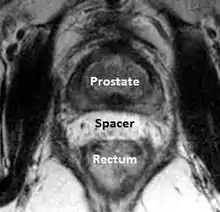

A new method to reduce rectal radiation injury in prostate cancer patients involves the use of an absorbable spacer placed between the prostate and rectum.

Such spacers are commercially available in some regions, and are undergoing clinical trials in others.[26] By temporarily altering the anatomy these products have the potential to allow for improved cancer targeting while minimizing risk to neighboring healthy tissues. Prostate Rectum Spacers should be compatible with all prostate cancer radiotherapy treatments including 3D conformal, IMRT and stereotactic radiation and brachytherapy.